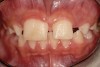

Fig 4 and Fig 5. The fused tooth was carved to resemble two teeth, matching the width of the created tooth central to tooth No. 9.

Using the wax-up as a guide, a composite restoration was fabricated for fused teeth Nos. 7 and 8 by roughening the affected area without pulpal exposure, etching the enamel, and applying primer and adhesive. Composite shade A1 was bonded to the mesial and distal surfaces, with gingival dark composite applied to the cervical “interproximal” region. The tooth was then carved to resemble two teeth, matching the width of the created tooth central to tooth No. 9 (Figure 4 and Figure 5). The patient and her family were very pleased with the result, and no postoperative sensitivity was reported.